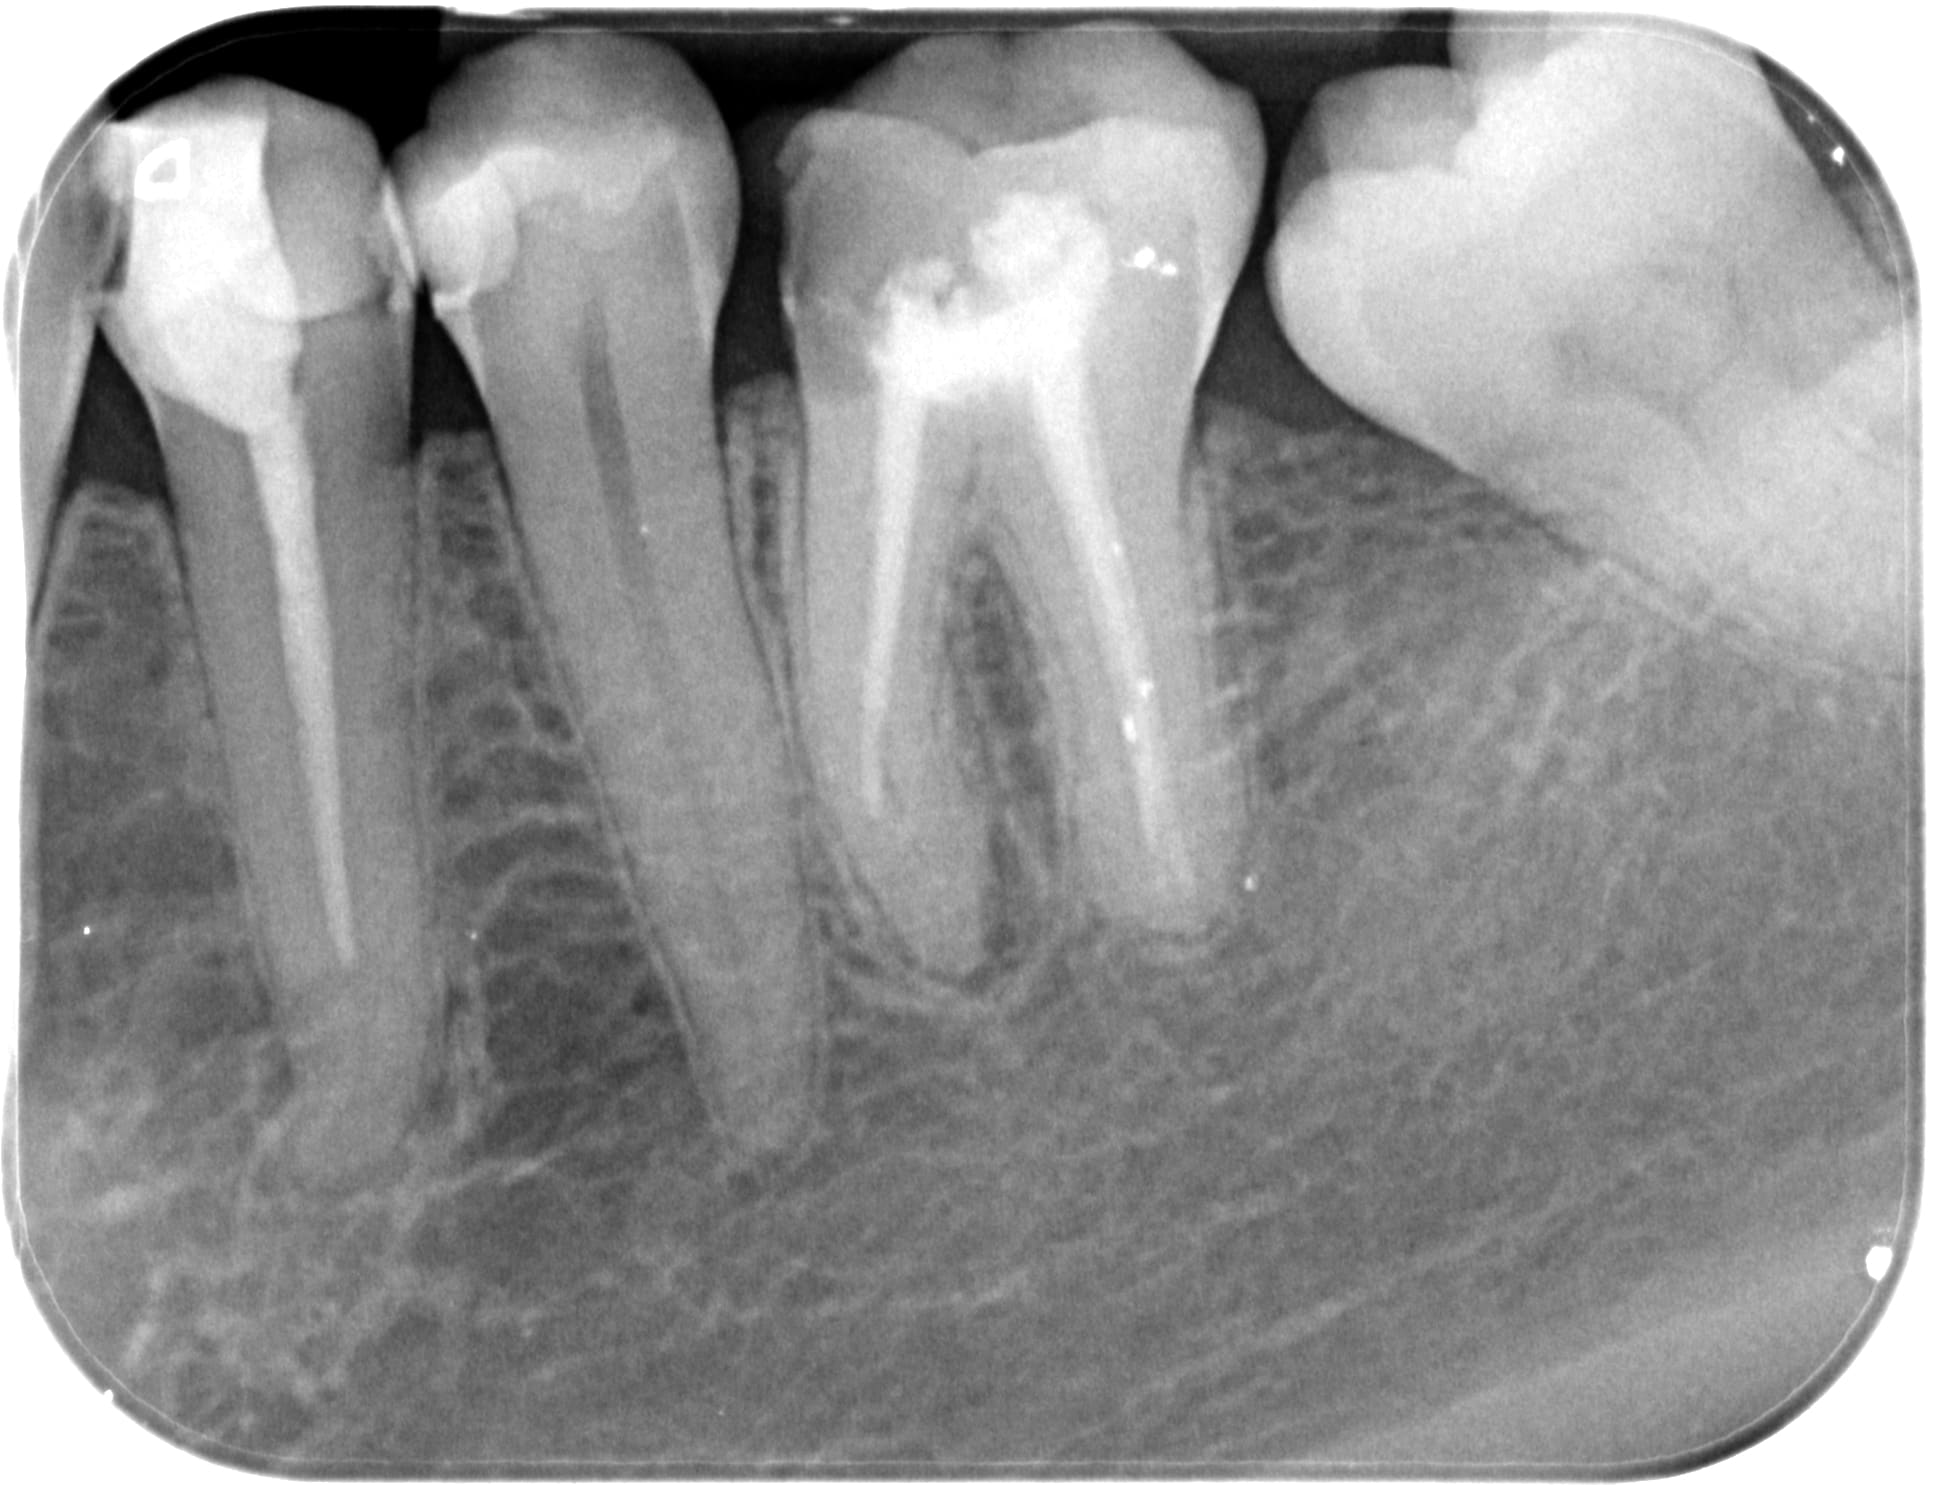

La j'ai repris les canaux mesiaux en manuel, lime k/H en alternance... l'ancien prat avait buté dans la courbure. La difficulté c'est biensur de retrouver les canaux et surtout de na pas continuer dans la fausse route.

Bon sinon le plancher cameral fin comme un papier a cigarette en effet c'est préoccupant…

La je temporise avec un énorme IRM.

Question purement théorique : pour moi la dent est perdue mais si des fois on envisageait de la conserver, une idée de la tenue dans le temps d'une obturation à la biodentine avec ce plancher ?

Ou alors vaut I'm mieux cureter ce qui reste et obturzr en direct au contact des tissus vivants environnants ?

La furcation semble contaminée et du coup on va essayer de l'atteindre à travers le plancher ou on espère une cicatrisation ?